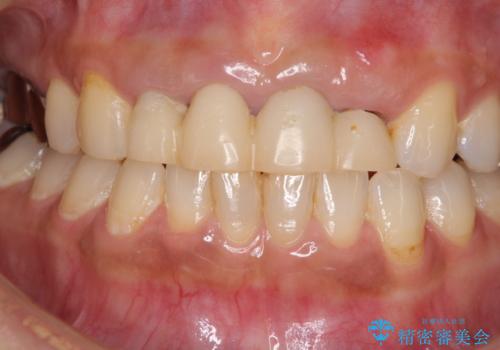

- 地元の歯科医院にて前歯4歯を仮歯に替えたものの、汚れていることが気になるとのことで来院された患者様です。

不適な仮歯の影響で歯肉が腫れていたため、新しい仮歯に替えた後に歯肉の腫れが引くのを待ち、オールセラミッククラウンにて補綴することとしました。

根尖病変が原因で、膿が出てきている歯があったため、仮歯を置き換える際に根管治療を行うこととしました。

仮歯を変えたことで歯肉の腫れは引き、根管治療も功を奏して膿の出口はきれいに消退しました。